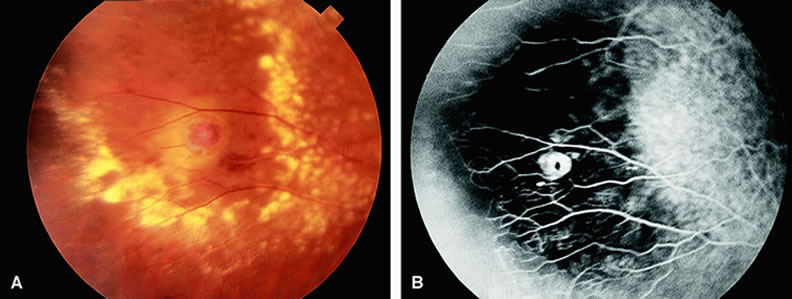

Coats' disease19 is a retinal vascular abnormality of unknown etiology characterized by retinal telangiectatic formations in association with intraretinal and subretinal hard exudates (Fig. 15). Focal areas of dilation and narrowing of the larger retinal vessels are often seen. Fluorescein angiography20 demonstrates hyperfluorescence of the telangiectatic vessels early in the study along with hypofluorescence of proteinaceous exudates and mild hyperfluorescence of subretinal fluid. Enlargement of the retinal capillary bed and widened spaces between these small vessels is characteristic of Coats' disease. Retinal capillary nonperfusion is often seen, but associated retinal neovascularization is rare. Leakage of dye can occur from both the larger and smaller vessel abnormalities.

Fig. 15. A. The midperipheral fundus of a patient with Coats' disease demonstrates a retinal telangiectasia surrounded by yellow and white hard exudates and intraretinal edema, as well as hemorrhage. B. Fluorescein angiogram of A shows hyperfluorescent telangiectatic capillary beds with hypofluorescent regions between the capillary beds, consistent with capillary nonperfusion.